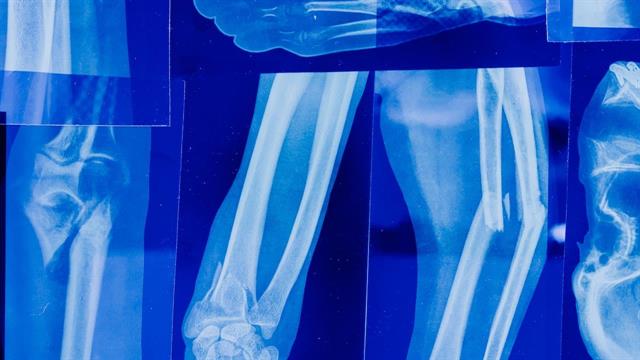

Ο Σύλλογος Σκελετικής Υγείας Πεταλούδα ανακοινώνει την έναρξη της καμπάνιας για την ευαισθητοποίηση του κοινού γύρω από την οστεοπόρωση με τίτλο «Είχες ποτέ Κάταγμα; Έλα να δούμε αν έχεις οστεοπόρωση!».

Στόχος της καμπάνιας είναι η ενημέρωση και η ευαισθητοποίηση του κοινού γύρω από τα κατάγματα και την οστεοπόρωση μέσα από μια σειρά εκδηλώσεων που θα γίνουν σε πανελλαδικό επίπεδο, καλύπτοντας από μεγάλα αστικά κέντρα μέχρι πιο μικρές κωμοπόλεις.

Κατά τη διάρκεια αυτών των εκδηλώσεων που στις περισσότερες περιοχές θα διαρκέσει 2-3 ημέρες, θα προσφερθούν δωρεάν εξετάσεις οστικής πυκνότητας και προσωπική συμβουλευτική από εξειδικευμένους επιστήμονες της κάθε περιοχής.